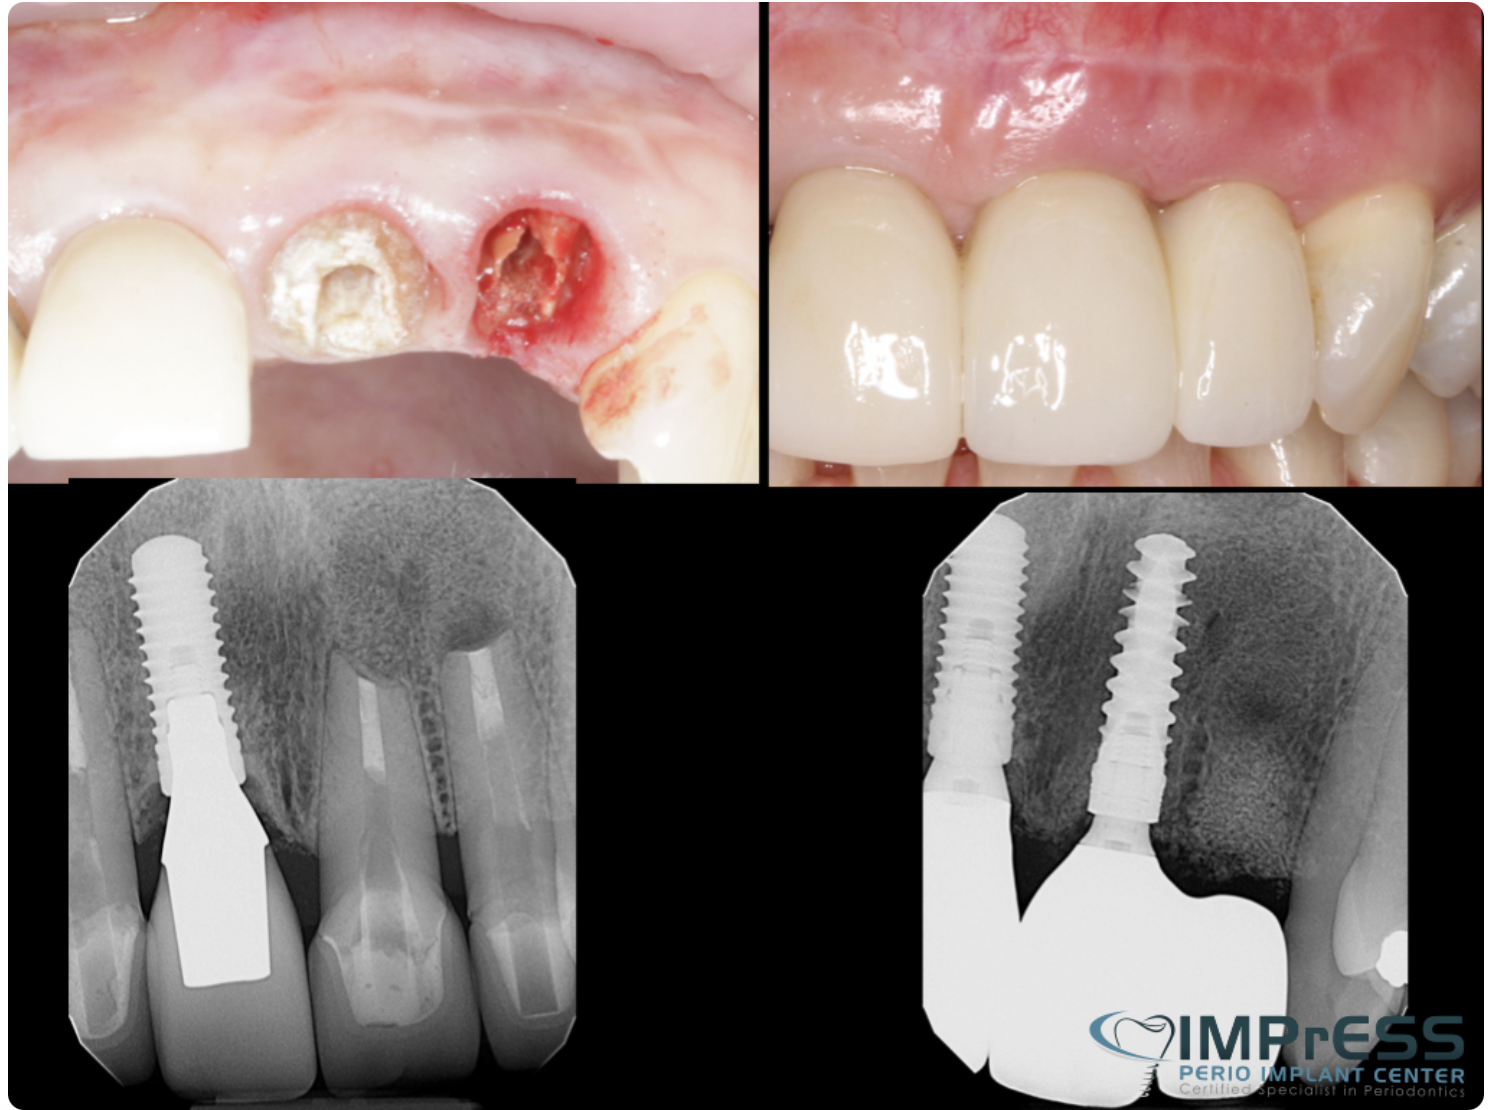

Before & Afters of Dental Implant Patients

Complete Dental Implant Cases Gallery

Dental implant treatment is sometimes a team effort between your periodontist and a restorative dentist.  Dr. Noroozi  at IMPrESS Perio Implant Center located in Burnaby BC performs the actual implant surgery, initial tooth extractions, and bone and gum grafting if necessary.  The restorative dentist (your dentist) or our specialists (if you do not have a dentist) will fit and make the permanent prosthesis. Your dentist or our specialists will also make any temporary prosthesis needed during the implant process.

General Disclaimer: The results in the photographs are examples only and do not imply any certainty of the result of a procedure, and all outcomes are subject to the circumstances of the individual patient.